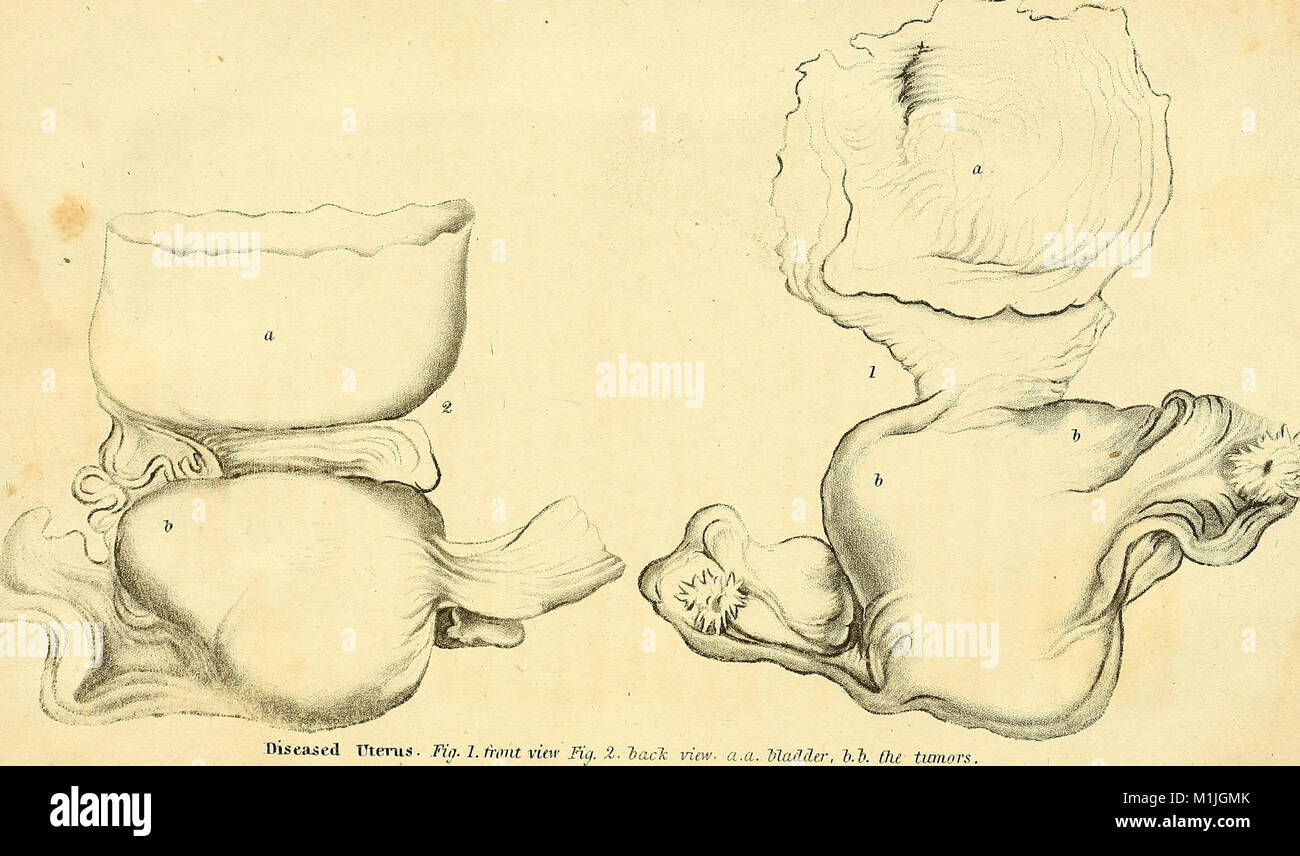

Anatomical investigations, comprising descriptions of various fasciae of the human body to which is added an account of some irregularities of structure and morbid anatomy; with a description of a new (17549108733) Stock Photohttps://www.alamy.com/image-license-details/?v=1https://www.alamy.com/stock-photo-anatomical-investigations-comprising-descriptions-of-various-fasciae-173126595.html

Anatomical investigations, comprising descriptions of various fasciae of the human body to which is added an account of some irregularities of structure and morbid anatomy; with a description of a new (17549108733) Stock Photohttps://www.alamy.com/image-license-details/?v=1https://www.alamy.com/stock-photo-anatomical-investigations-comprising-descriptions-of-various-fasciae-173126595.htmlRMM1JGMK–Anatomical investigations, comprising descriptions of various fasciae of the human body to which is added an account of some irregularities of structure and morbid anatomy; with a description of a new (17549108733)